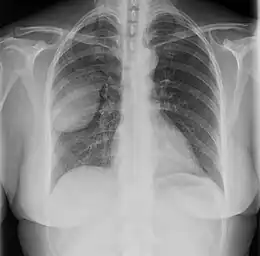

Les tumeurs fibreuses solitaires pleurales sont visualisées sur la radiographie thoracique comme des masses bien délimitées. Les clichés radiologiques standards sont cependant peu utiles pour les autres localisations[17].